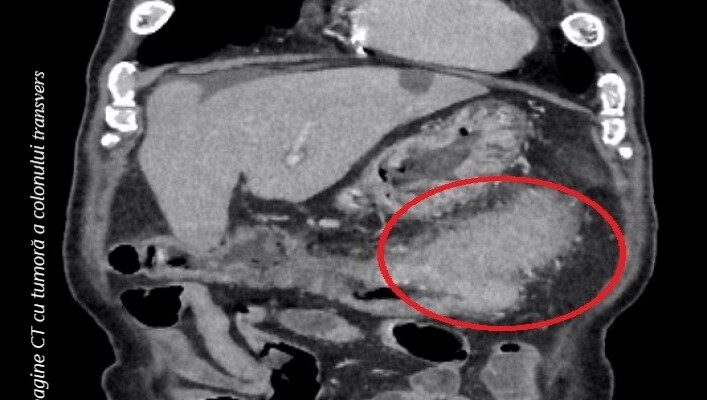

ROLUL COMPUTER-TOMOGRAFIEI ÎN MANAGEMENTUL CANCERULUI COLORECTAL

Computer-tomografia (CT) este o investigație imagistică recomandată pentru multiple afecțiuni. Această explorare utilizează radiațiile X pentru a crea imagini detaliate despre structuri normale și patologice ale organismului. În cancerul colorectal, CT-ul permite vizualizarea și localizarea formațiunii tumorale aflate la nivelul...